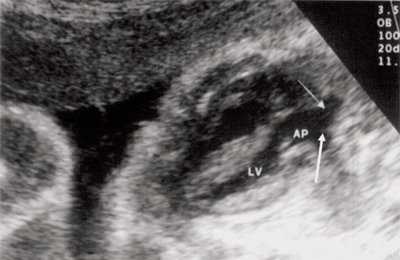

В равной степени это относится к дефекту межжелудочковой перегородки (рис. 6), простой форме транспозиции магистральных сосудов (рис. 7, 8), транспозиции магистральных сосудов с дефектом межжелудочковой перегородки (синдром Тауссиг - Бинга) (рис. 9), общему желудочку (рис. 10), общему артериальному стволу (рис. 10), двойному отхождению сосудов от одного из желудочков сердца (рис. 11).

Рис. 9. Синдром Тауссиг - Бинга. Легочная артерия (отмечена стрелкой) расположена над дефектом межжелудочковой перегородки.

Рис. 10. Общий желудочек с отхождением TRUNCUS ARTERIOSUS. Стрелками показано разделение TRUNCUS ARTERIOSUS на аорту и ствол легочной артерии.

LV и RV - левый и правый желудочек, АР - легочная артерия, АО - аорта, VSD - дефект межжелудочковой перегородки.